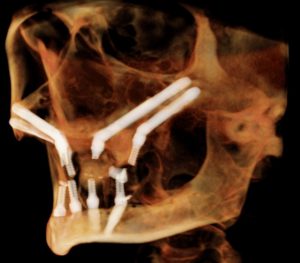

Two Zygomatic implants in addition to four traditional implants. This patient had a “strong” bite and a history of grinding his teeth, necessitating extra support.